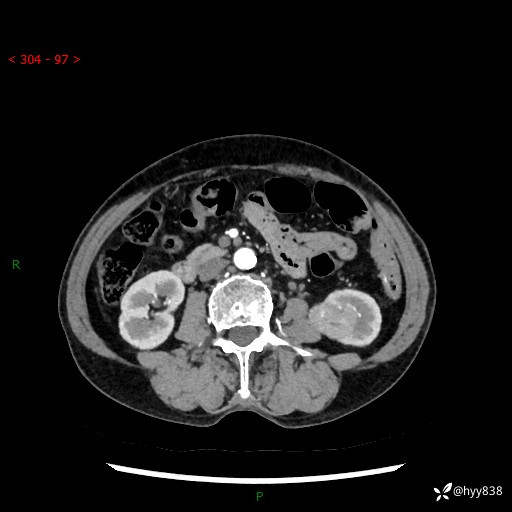

72岁/女,检查发现左肾占位1天。为了满足诊断,常规四期后,又加了延迟期-结果公布~

【患者信息】:72岁/女

【主诉】:检查发现左肾占位1天

【现病史及既往史】:患者于1天前检查发现左肾占位,无畏寒发热,无咳嗽咳痰,无腰腹部疼痛不适,无肉眼血尿、无尿频尿急症状,起病来,患者未行特殊治疗,为求进一步诊治,门诊以"左肾占位"收治入院。 发病来患者精神、饮食、睡眠良好,小便如上,大便正常,体重无明显变化。

【检查】:肾脏CT平扫+增强